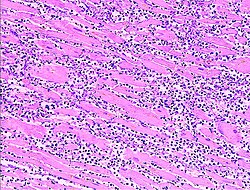

[edytuj | edytuj kod]Dokonany zawał mięśnia sercowego pod względem morfologicznym jest zawałem bladym, w którym pojawia się martwica skrzepowa (denaturacyjna). Na obrzeżach ogniska zawałowego mogą powstać ogniska uszkodzenia reperfuzyjnego, w wyniku którego pojedyncze kardiomiocyty ulegają martwicy rozpływnej[19][20].

Makroskopowo zawał jest obszarem bledszej oraz mniej spoistej tkanki niż otaczający mięsień, otoczony wąskimi pasami (rąbkami) barwy czerwonej i żółtej[19][20].

Jeśli zawał pełnościenny jest niepowikłany, typowo przebiega on w czterech okresach[19][20]:

- zawał wczesny (łac. infarctus myocardii recens) w pierwszych kilkunastu godzinach od dokonania martwicy. W tym czasie obszar zawału ujawnia się morfologicznie: pojawia się tzw. rąbek czerwony (pas przekrwienia na obrzeżu ogniska) oraz rąbek żółty (pas granulocytów obojętnochłonnych ulegających stłuszczeniu na obrzeżu ogniska), włókna mięśniowe ulegają fragmentacji i zanika ich poprzeczne prążkowanie

- zawał w stanie rozmiękania (łac. infarctus myocardii in statu emollitionis) trwa od drugiej do dziesiątej – czternastej doby. W tym okresie granulocyty obojętnochłonne i makrofagi uprzątają martwą tkankę, a następnie dochodzi do proliferacji naczyń włosowatych

- zawał w okresie organizacji (łac. infarctus myocardii in statu organisationis) następuje w trzecim i czwartym tygodniu po dokonaniu zawału. Organizacja zawału polega na rozplemie tkanki ziarninowej w miejscu uprzątniętej martwicy

- kształtowanie się blizny pozawałowej (łac. cicatrix post infarctum myocardii) trwa od drugiego do szóstego miesiąca po zawale. Formowanie blizny polega na przekształceniach tkanki ziarninowej, w której przybywa włókien kolagenowych.